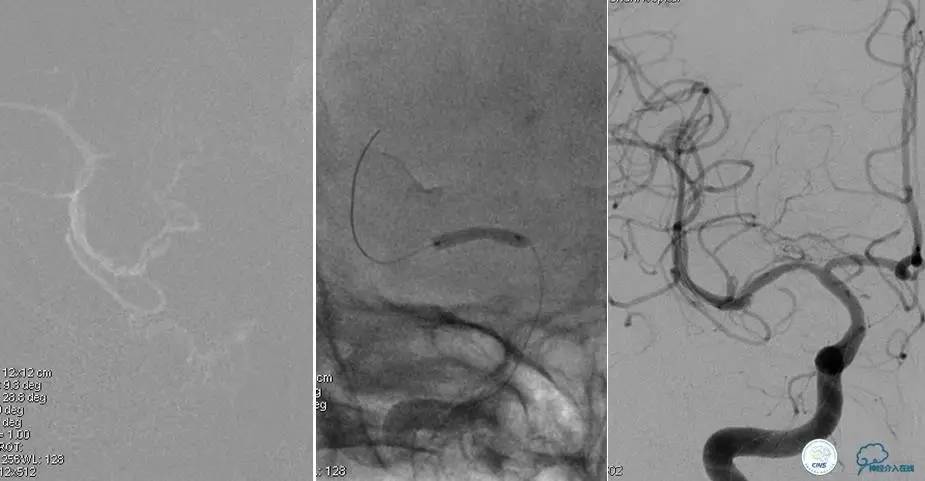

患者:53岁男性,反复脑梗死3个月。

▼给予球囊扩张成形,闭塞段较长,决定药物治疗视察,二期再给予支架治疗。

▼药物治疗1个月,再次发作。再次来我院支架治疗。

▼支架术后,效果好。

因此,某些患者分期治疗也具有合理性。